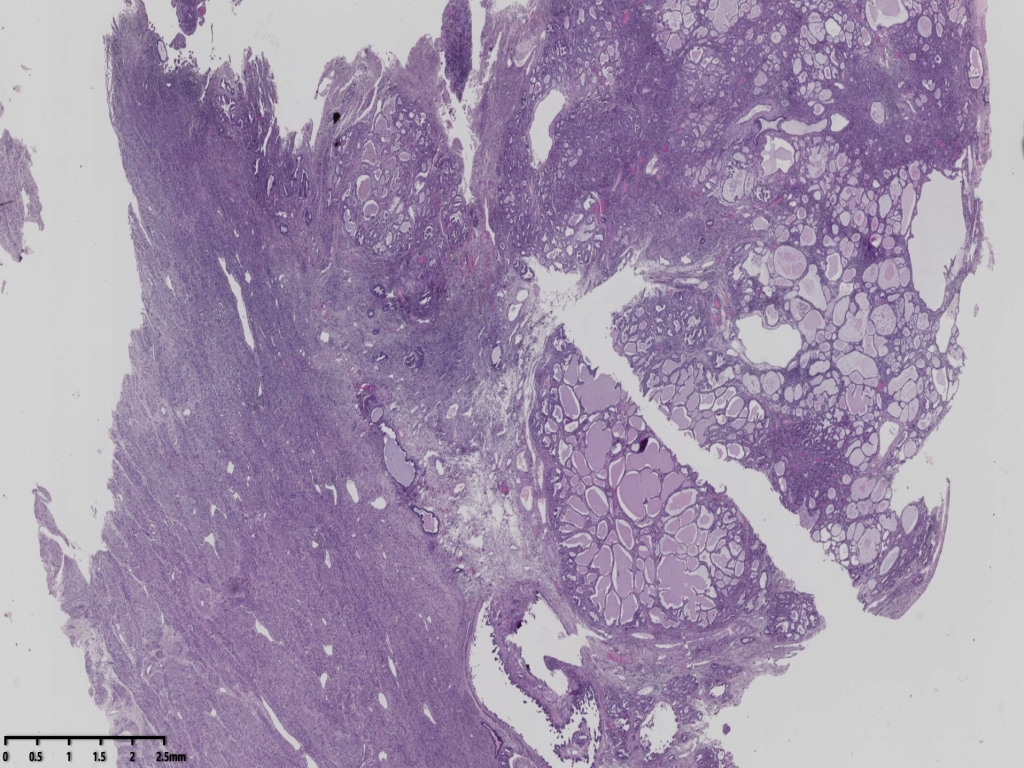

大体标本可见子宫后壁靠近宫底可见一个突出内膜面的肿物,体积约3*2*2厘米,广基,切面灰白,实性,质地脆,其余内膜略粗糙。

镜下可见肿物,腺样机构,密集,细胞异型

局部分区域腺体偏实性,细胞核大,周围胞浆空亮,会诊为子宫透明细胞癌,是不是就依据这一点?

但是其余部位内膜可见微乳头结构。

宫颈管及宫颈管可见癌组织侵犯浅层,以腺样结构为主

癌组织侵及子宫壁浅层,小于1/2,累及宫颈浅层。